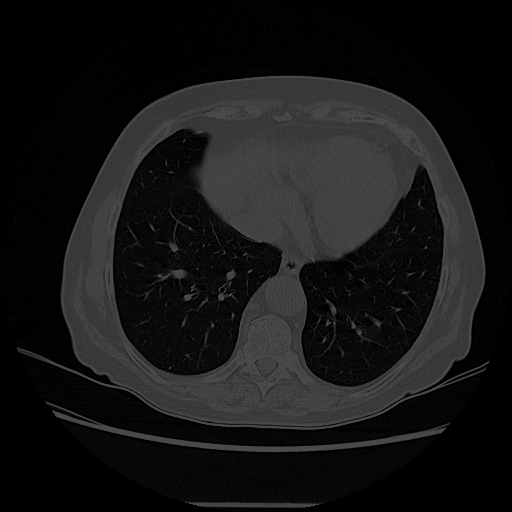

Original NATIVE CT scan (input)

Full window (WL 1023.5, WW 4095 β†’ Low βˆ’1024, High +3071)

Lung window (WL -600, WW 1500 β†’ Low βˆ’1350, High +150)

Mediastinum window (WL 40, WW 400 β†’ Low βˆ’160, High +240)